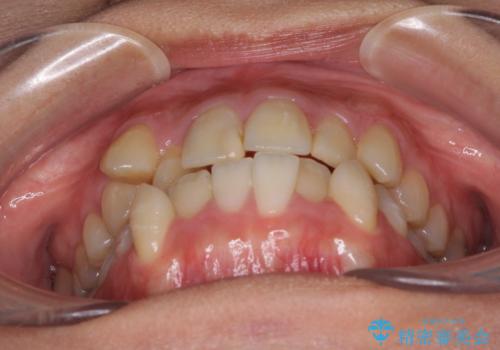

- 上下の八重歯を気にして来院された患者様です。

八重歯の後ろの歯を1歯抜歯し、補助装置(リンガルアーチ)を用いて八重歯の位置を改善し、その後インビザラインにより矯正治療を行うこととしました。

右側のみ上下小臼歯を抜歯したため、上下の正中が右にずれてしまう可能性があります。

また、元々右側は上下が咬み合っていないため、矯正をしても咬み合わないことも考えられました。

治療期間はかかりましたが、正中も合い、綺麗な仕上がりとなりました。